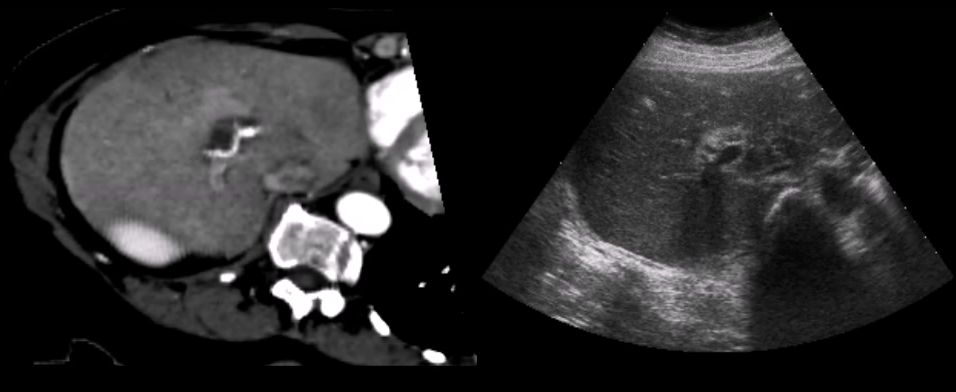

In addition, co-registration techniques enable use of multi-modal data sets. Fusion imaging, where ultrasound is combined with either CT, MRI, or PET images, allows for more precise navigation in ultrasound-guided interventions. This challenging new arena demands advanced visualization research to enlighten how different data types can be combined and presented in novel ways.

5 Registration

Merging ultrasound with other modalities can be very beneficial. While ultrasound provides high resolution images at a high frame-rate, other modalities, such as MRI or CT can provide information complimentary to the ultrasound images. Data registration is the process of transforming different modalities into the same reference frame to achieve as much comprehensive information about the underlying structure as possible. While CT and MRI are typically pre-operative imaging techniques, ultrasound can easily be performed live during surgery. For instance, the radiation from CT is dangerous and the large electro magnets in a MRI scanner require that everything in the room is non-magnetic. Recently Curiel et al. built a non-magnetic ultrasound scanner for proper simultaneous intra-operative imaging curiel07 . There where some electric interference between the two modalities. Yet, the technique is promising, although availability will most likely be very low.

Nikas et al. published an evaluation of the application of co-registered 2D ultrasound and MRI for intra-operative navigation nikas03 . Ultrasound based navigation shows promising results due to live acquisition at high frame rates and easy portability. For prostate brachytherapy a combination of ultrasound and co-registered CT can be used, as shown by Fuller et al. fuller05 . Existing commercial products apply optical tracking for intra-operative navigation during neurosurgery sonowand11 . Figure 5 shows how ultrasound and MRI can be blended together into a single reference frame burns07 .

Penney et al. proposed a technique for registering MRI and ultrasound. The system calculates a probability map of each element being a part of a liver-vessel penney04 . Later Penney et al. extended their technique for CT-ultrasound registration of the pelvis and femur penney06 . The system was validated using cadavers, showing that the registration was accurate to a 1.6mm root-mean-square error on average. A similar technique for the cardiovascular domain was proposed later by Zhang et al.zhang06 .

External pressure or different laying positions of the patient when acquiring the images. To account for local deformations while imaging soft tissue, a more complex registration is required. Papenberg et al. proposed two approaches for CT ultrasound registration papenberg08 given a set of paired landmarks in both the CT and ultrasound data-set. One approach use the landmarks as hard constraints and in the other, the landmarks are considered as soft constraints and are combined with intensity value information, in this case the normalized gradient field. The paper shows a non-rigid registration between the liver vascular structures. The latter technique was later evaluated by Lange et al. lange08 .